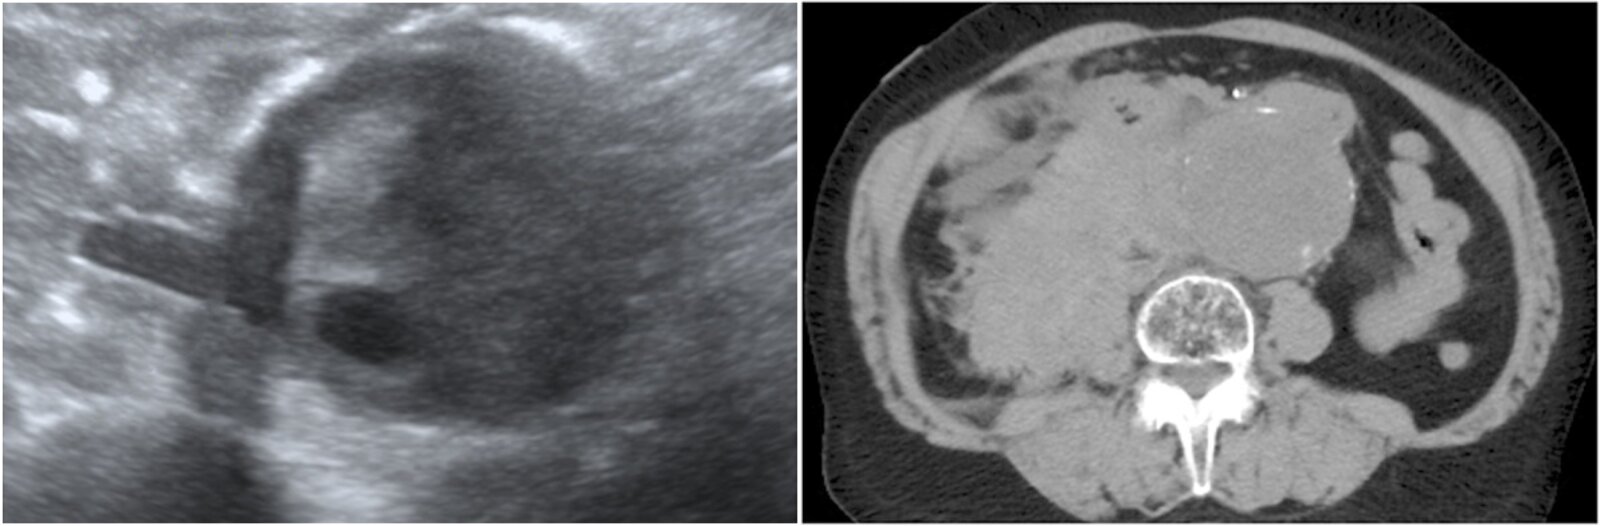

Abdominal ultrasound (formal ultrasound or POCUS)

-

Indications

Best initial and confirmatory test in:

- Asymptomatic patients

- Patients with abdominal pain and no known AAA or risk factors for AAA

- To determine the presence, size, and extent of an aneurysm

- Screening and surveillance

Formal ultrasound [8]

- Obtain longitudinal and transverse views for:

- Proximal, mid, and distal abdominal aorta

- Both proximal common iliac arteries

- Obtain AP dimension measurements of the greatest diameters of each vessel.

- See āPOCUS for suspected AAAā for the point-of-care imaging technique and findings.

Supportive findings

- Dilatation of the aorta ā„ 3 cm [1]

- Thrombus may be present (hyperechoic)

- Disadvantages: Abdominal ultrasound has low sensitivity for aneurysmal leaks, branch artery involvement, and suprarenal involvement, and its findings are insufficient for procedural planning. [1][9]

![]()

If a large (ā„ 5.5 cm in men, ā„ 5.0 cm in women) aneurysm is seen on ultrasound in a patient presenting with abdominal pain, refer the patient for treatment immediately.